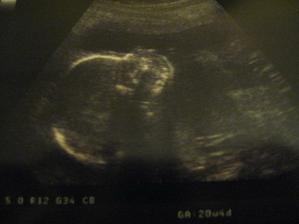

2. 3. 2011 Dneska jsme se byli vyfotit ve 3D 🙂 Chtěli jsme i video ale Kačenka měla půlnoc tak nebylo co točit 🙂